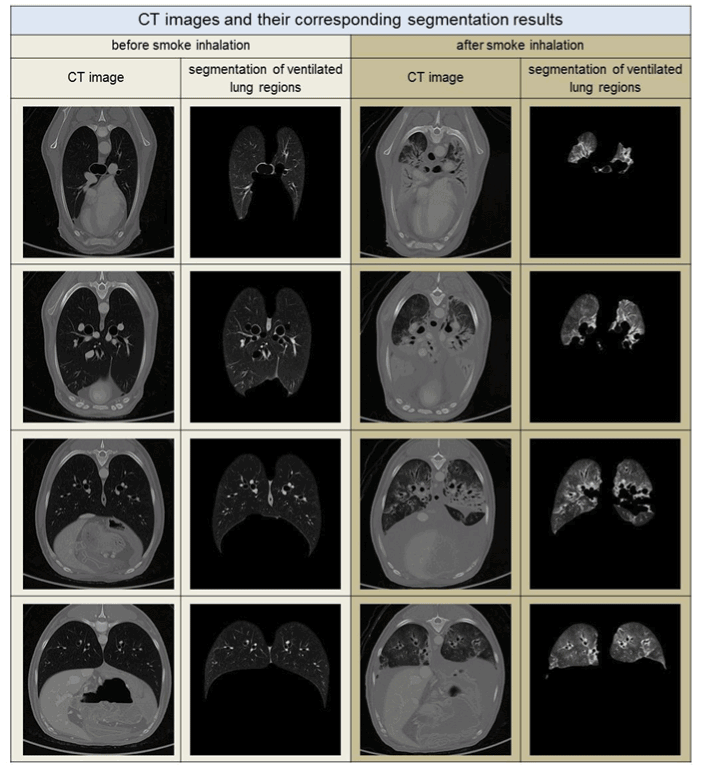

Lung segmentation: Methods of lung segmentation are well established [8-10]. The lung segmentation approach used in this study is described in detail in ref. [11]. An adapted threshold segmentation, guided by the low radiation attenuation of ventilated lung tissue, was applied. This approach segments those parts of the respiratory system, including the trachea and lung tissue, that correspond to the anatomical definition of a healthy lung, in which the complete lower respiratory system is partitioned. In contrast, in the case of a lung heavily affected by smoke, the segmentation approach excludes radiologically denser lung tissue. See the segmentation examples in Figure 1.

Figure 1. CT images with the corresponding segmentation results for air-filled lung regions sup-porting gas-exchange. Each column shows sectional images before and after smoke inhala-tion for similar thoracal positions. The position of the thorax changes in each row from proxi-mal to distal, top to bottom

The segmentation process of the CT images “before” and “after” smoke inhalation that was fundamental to this numerical investigation was guided by the low radiation attenuation of lung tissue that contains air. For the healthy lung, this segmentation approach agrees completely with the anatomical definition of the lung shape defined as the lower respiratory sys-tem. By contrast, very radiologically dense areas in the smoke-affected lung are not completely segmented (Figure 1). Such missing regions may have HU values that are as dense as heart tissue. Although our segmentations of the smoke-affected lungs were partially incomplete, the segmentation approach was considered entirely satisfactory, as it allowed a significant differentiation between the two experimental groups by various morphometric parameters. In this pragmatic approach, this was all that was desired. Moreover, it is interest-ng to note that a group differentiation could, in particular, be achieved in the denser HU value ranges, beginning roughly with subsets at L[-550,-501] and denser. This indicates that enough of the denser tissue was segmented to make group differentiations possible. In these dense subsets, the volume was larger after smoke inhalation than before the inhalation procedure. At first, this finding is astonishing, given that the average complete volume of the lung decreased dramatically after smoke inhalation, see Table 1, but, with the volume data in mind, it is easy to understand the density behavior in the denser HU subset ranges: Since a larger volume of voxels with higher density can be found after smoke inhalation, the density necessarily also increases after smoke inhalation compared to the density before smoke in-halation (Figure 5). The fractal dimension spectrum of the denser HU subsets in Figure 5 can be understood when one considers the volume and density properties within these sub- set ranges: The volume and the density increase after smoke inhalation compared to the status before the inhalation event. Since the fractal dimension is, in a certain way, a measure of the space-filling ability of a geometrical set, see Figure 4, the fractal dimension also increases after the smoke inhalation event.